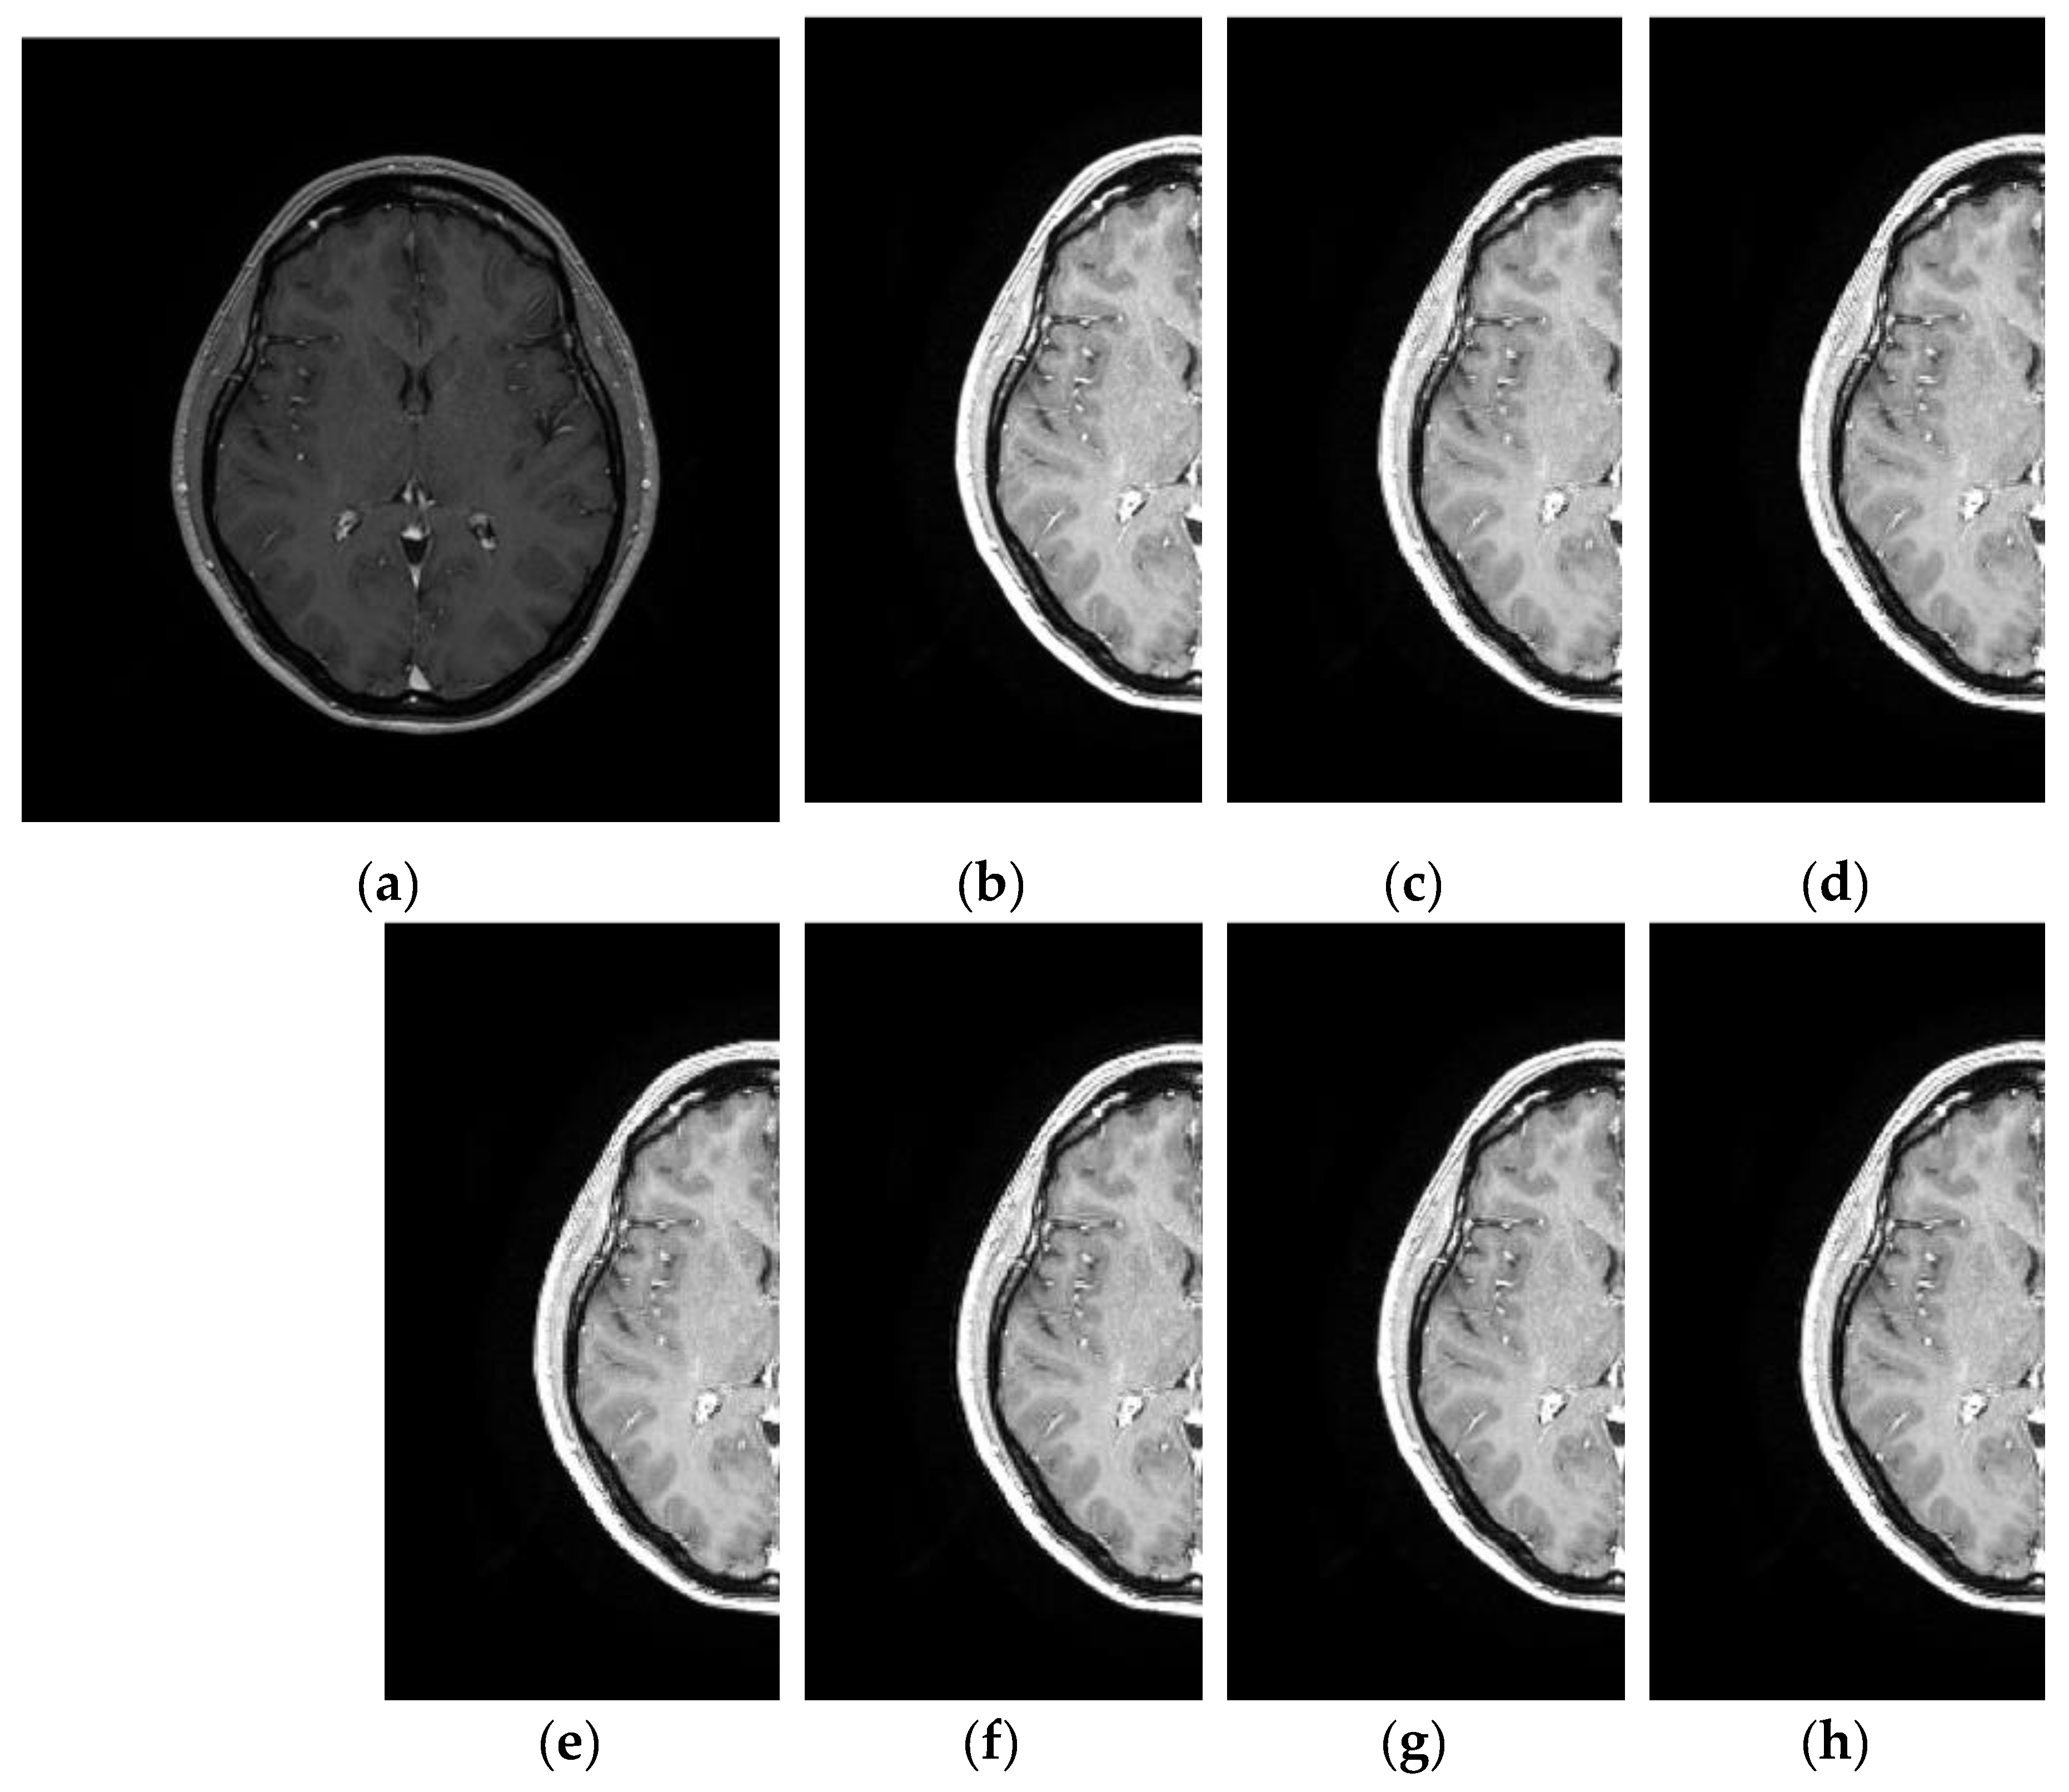

3.4. Comparative Performance in Real MRI